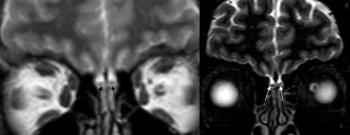

Scans show greater amyloid accumulation in the brains of older adults who get less than six hours sleep nightly.